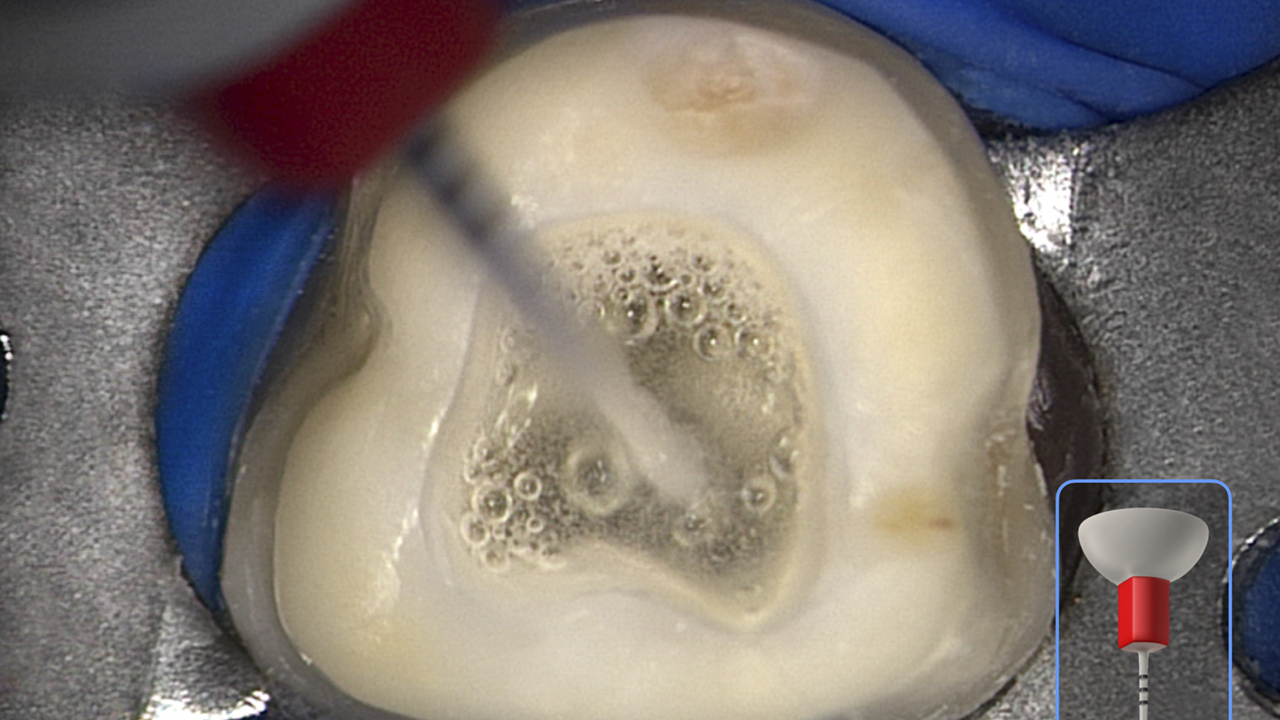

Deep Shape in Endodontics: Significance, Rationale and Benefit

The goal of endodontic treatment is to prevent or cure, when present, Lesions of Endodontic Origin, at times referred to as apical periodontitis. The role of bacteria in the pathogenesis of endodontic disease is well established, and therefore, it is critical to eradicate these pathogens by employing the highest level of presently developed standards. This … Read more